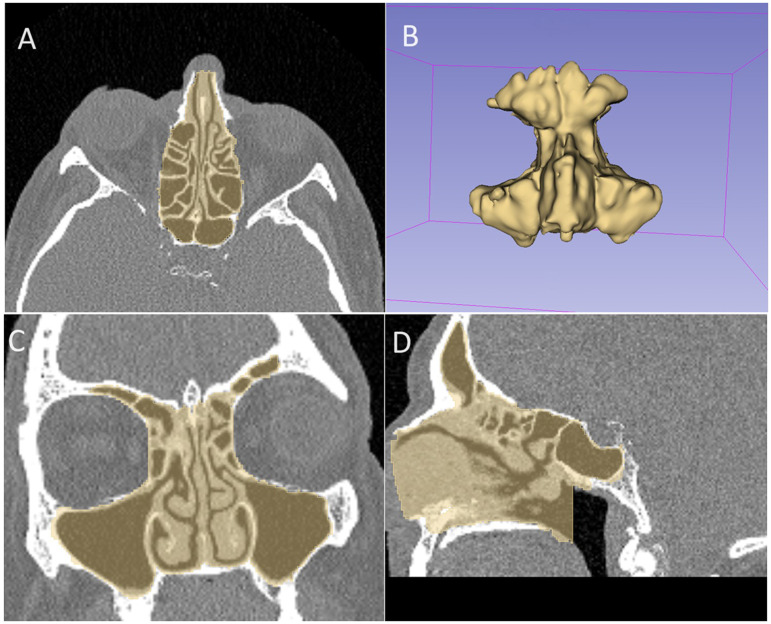

Abstract Image